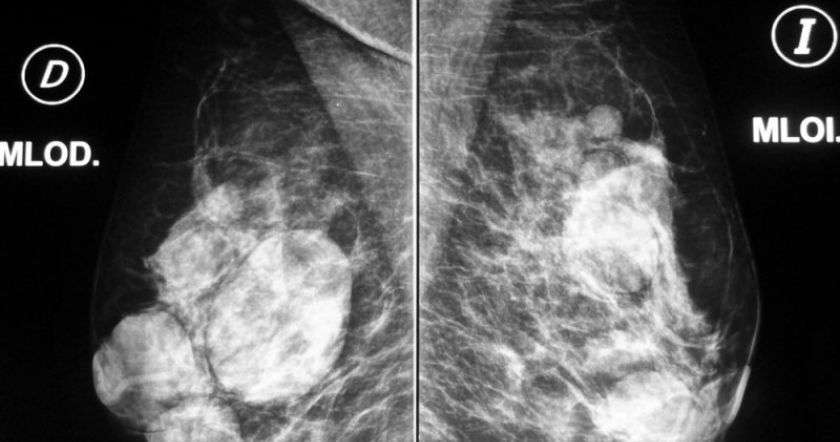

Ученые подчеркивают, что такая технология будет давать намного меньше ложноположительных результатов, которые нередко появляются при классической маммографии.